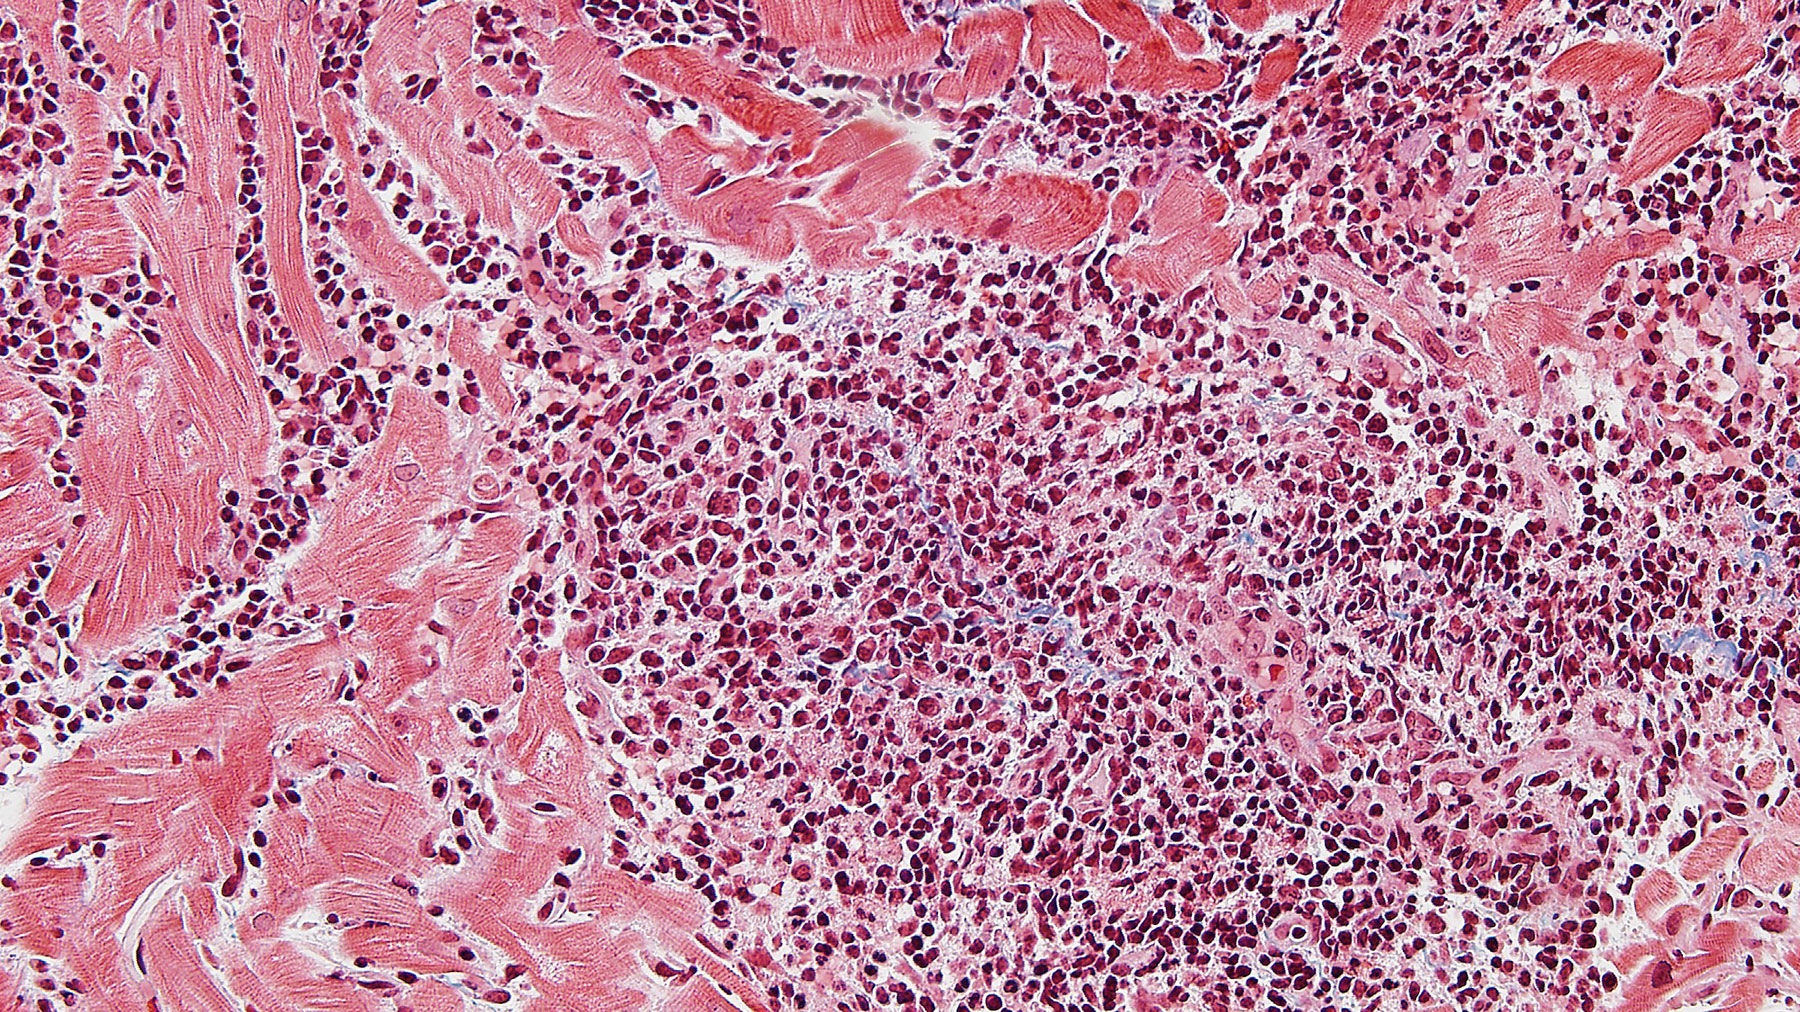

Figure A. H&E x10

Histology: Biopsy of the myocardial tissue performed at one month after the transplant showed myocardial tissue with diffuse and severe polymorphous mononuclear infiltrates with extensive myocyte damage, interstitial edema, vasculitis and focal necrosis (H&E staining in Figures A, C & E, and corresponding trichrome stains in Figures B, D & F). Special immunohistochemistry (IHC) stain for CD4 in a consecutive section from E and F (Figure G) shows a predominant infiltrate for helper cells.  All these features are consistent with severe acute cellular rejection, ISHLT 2004 Grade 3R (ISHLT 1990 Grade 3B).